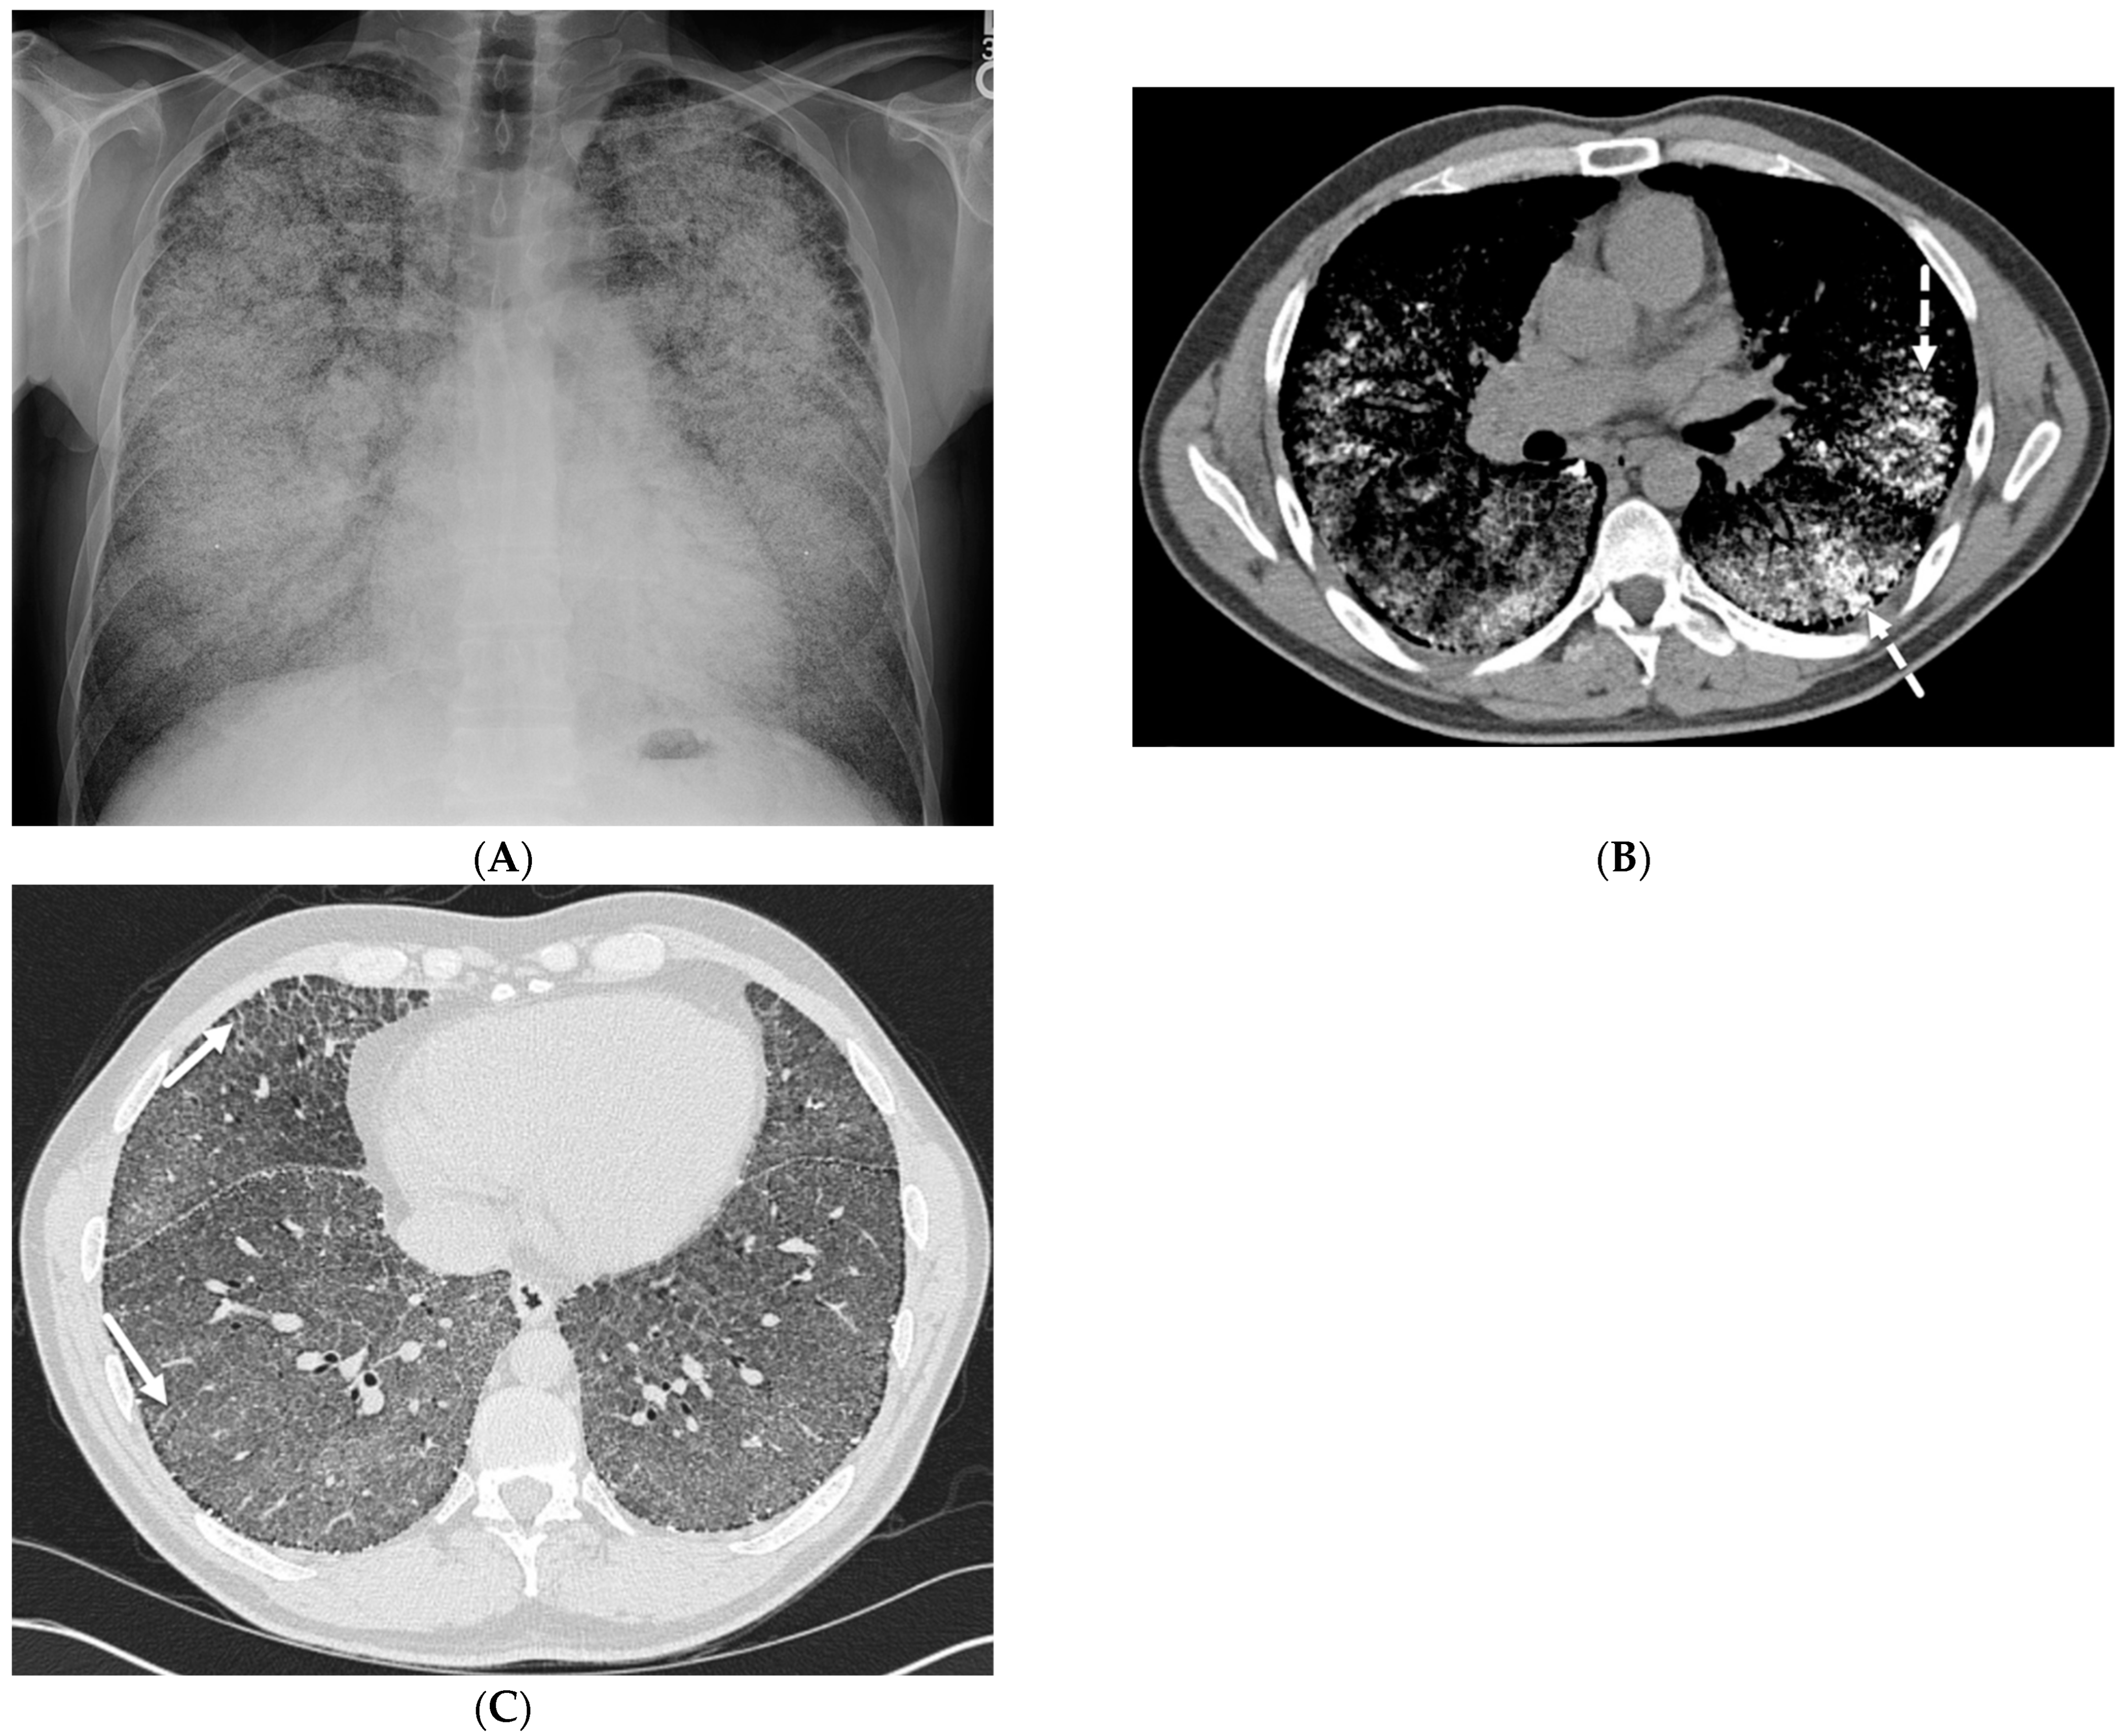

8.1. Diffuse Alveolar Hemorrhage (DAH)

8.2. Granulomatous–Lymphocytic Interstitial Lung Disease (GLILD)